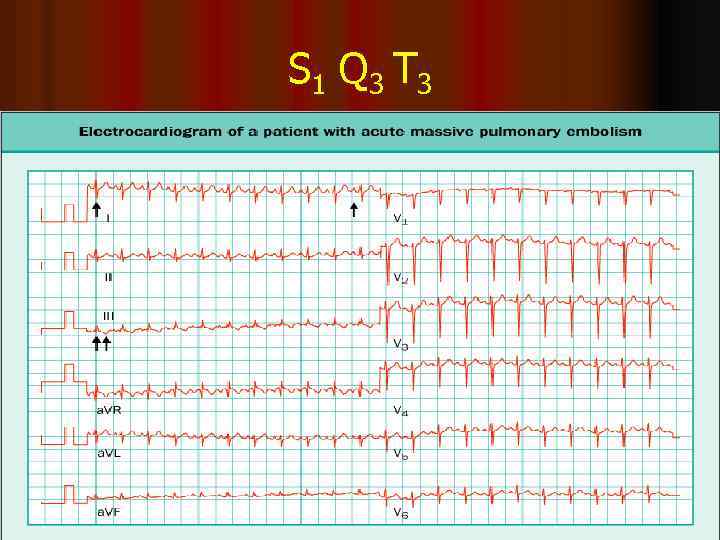

S 1 Q 3 T 3

Диагностика ТЭЛА l Клиническая вероятность l Анализ на D-димеры l Результаты СКТ / ангиопульмонографии